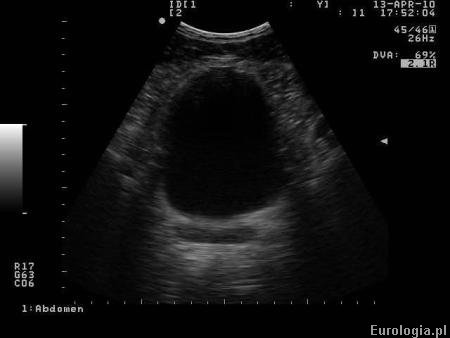

Fot. Pęcherz moczowy w badaniu USG

Dobrze wypełniony pęcherz moczowy jest podstawą jego oceny w badaniu USG. Pęcherz moczowy w czasie badania USG stanowi okno akustyczne, dzięki któremu możliwa jest ocena objętości gruczołu krokowego i otaczających struktur. Dobrze wypełniony pęcherz moczowy jest warunkiem miarodajnej oceny pod kątem obecności guzów lub kamicy.